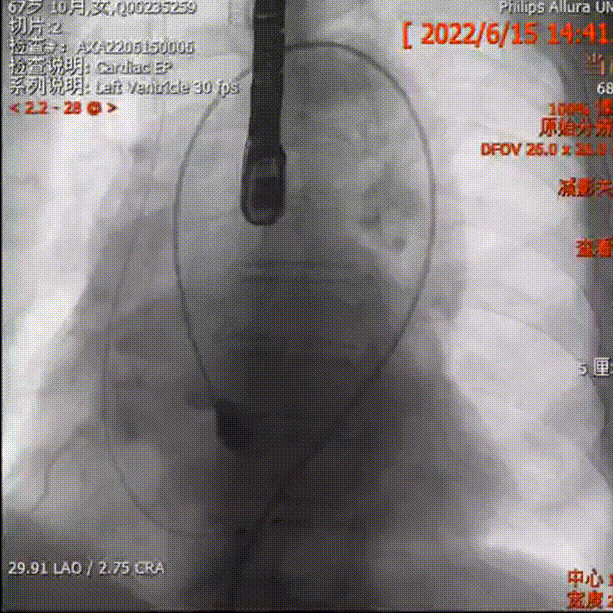

主动脉根部造影

2.根据当前影像及测量数值,推荐 LAO 30° CRA 10°(右窦中心位)左右跨瓣;